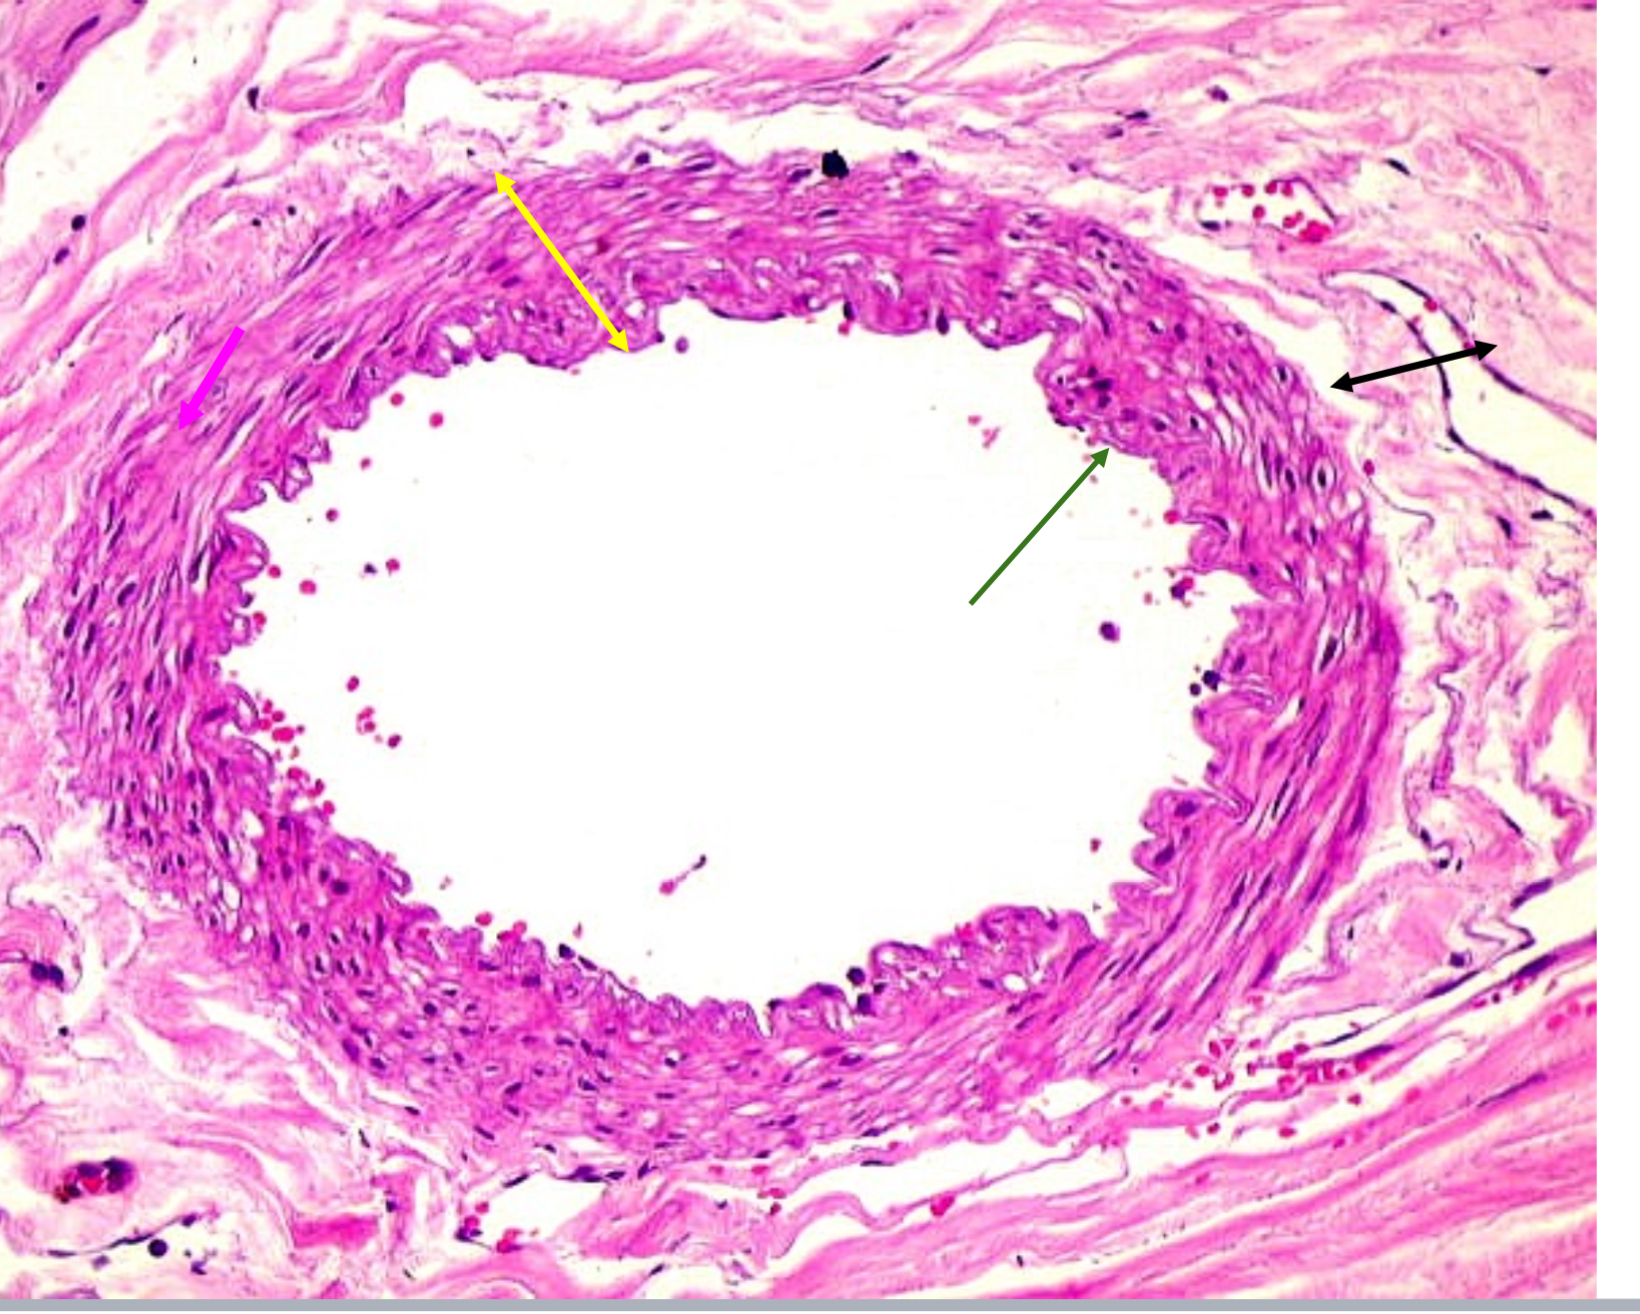

Tunica intima

Name the blue arrow

Lines lumen and release vasoactive chemicals

Function of tunica intima

Tunica media

Name green arrow

Vasoconstriction and vasodilation

Function of tunica media

Tunica externa

Name the purple arrow

Anchor and bind vessel

Function of tunica externa

Artery

Artery or vein?

Tunica intima

Name the green arrow

Tunica media

Name the yellow

Tunica externa

Name the black